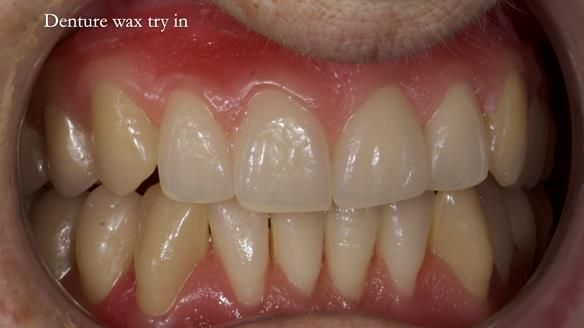

Welcome to Newsletter 83. This month I am sharing Sheila’s case — a very challenging but rewarding complete denture case. Sheila had flat ridges, a small mouth opening, a large tongue and had never been able to wear complete dentures of any kind. Everything was loose and sore. She felt embarrassed and looked older without dentures. She wanted a stable, comfortable result, and she wanted to avoid implants because she has taken bisphosphonates for more than five years.

In this newsletter I will take you through Sheila’s full protocol step by step — including impressions, French Impression Technique, Dr Abe shaping, copying Kirsty MacColl’s smile, the try-in, the final fit, and the copy dentures we made afterwards.